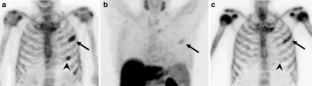

Fig. 1

Fig. 2

Fig. 3

Fig. 4

Fig. 5